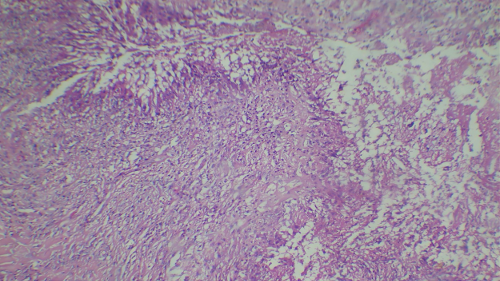

Upon microscopic examination, sections showed a well-circumscribed necrotizing lesion with palisading granulomas containing giant cells (Figure 3 [Fig. 3]). There were also areas of an old hemorrhage and cholesterol cleft formation. Staining for acid-fast bacteria was negative. The periodic-acid Schiff with diastase (PAS-D) stain (Figure 4 [Fig. 4]) and Grocott’s methenamine silver (GMS) stain both showed branching, septate fungal hyphae (Figures 5 [Fig. 5]). The diagnosis of a fungal abscess consistent with subcutaneous phaeohypomycosis was made, since the lesion was well circumscribed. No immediate antifungals started. Anti-diabetic measures were implemented and followed very strictly. The patient showed no recurrence or dissemination during 10 months of follow-up.

Figure 3: Hematoxylin and Eosin staining (40x) showing a necrotizing lesion with palisading granulomas containing giant cells